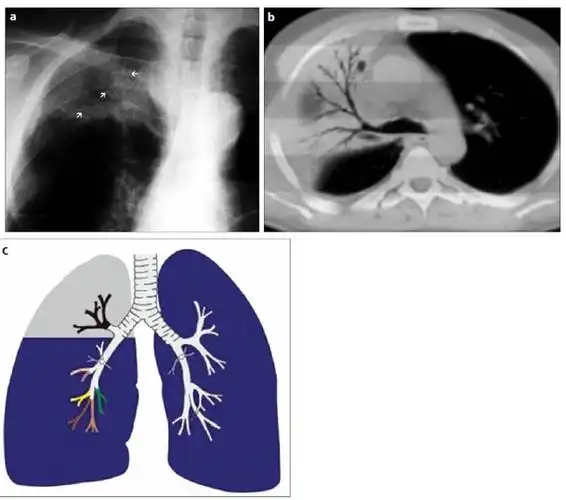

右上肺叶因放射性肺炎导致的实变伴空气支气管征.